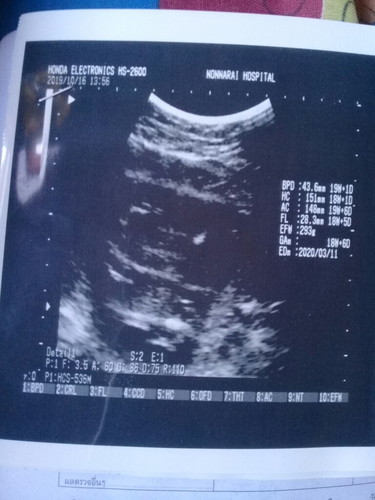

เข้า5เดือนแล้ว ลูกน้ำหนัก293 กรัมเอง ถือว่ายุในเกณฑ์ไหมค่ะ??

5เดือนน้ำหนักลูกเกณฑ์จะอยู่ประมาน300กรัมค่ะลองอ่านที่สมุดสีชมพูที่คุณหมอให้มาดูค่ะ

ยังต่ำคะ มันจะอยู่ประมาน 300กรัมเกือบ400กรัมถึงจะอยู่ในเกณต์คะ ดูตามแอปนี้นะคะ

20 วีคต้องได้ 300กรัมจ้ะขั้นต่ำ